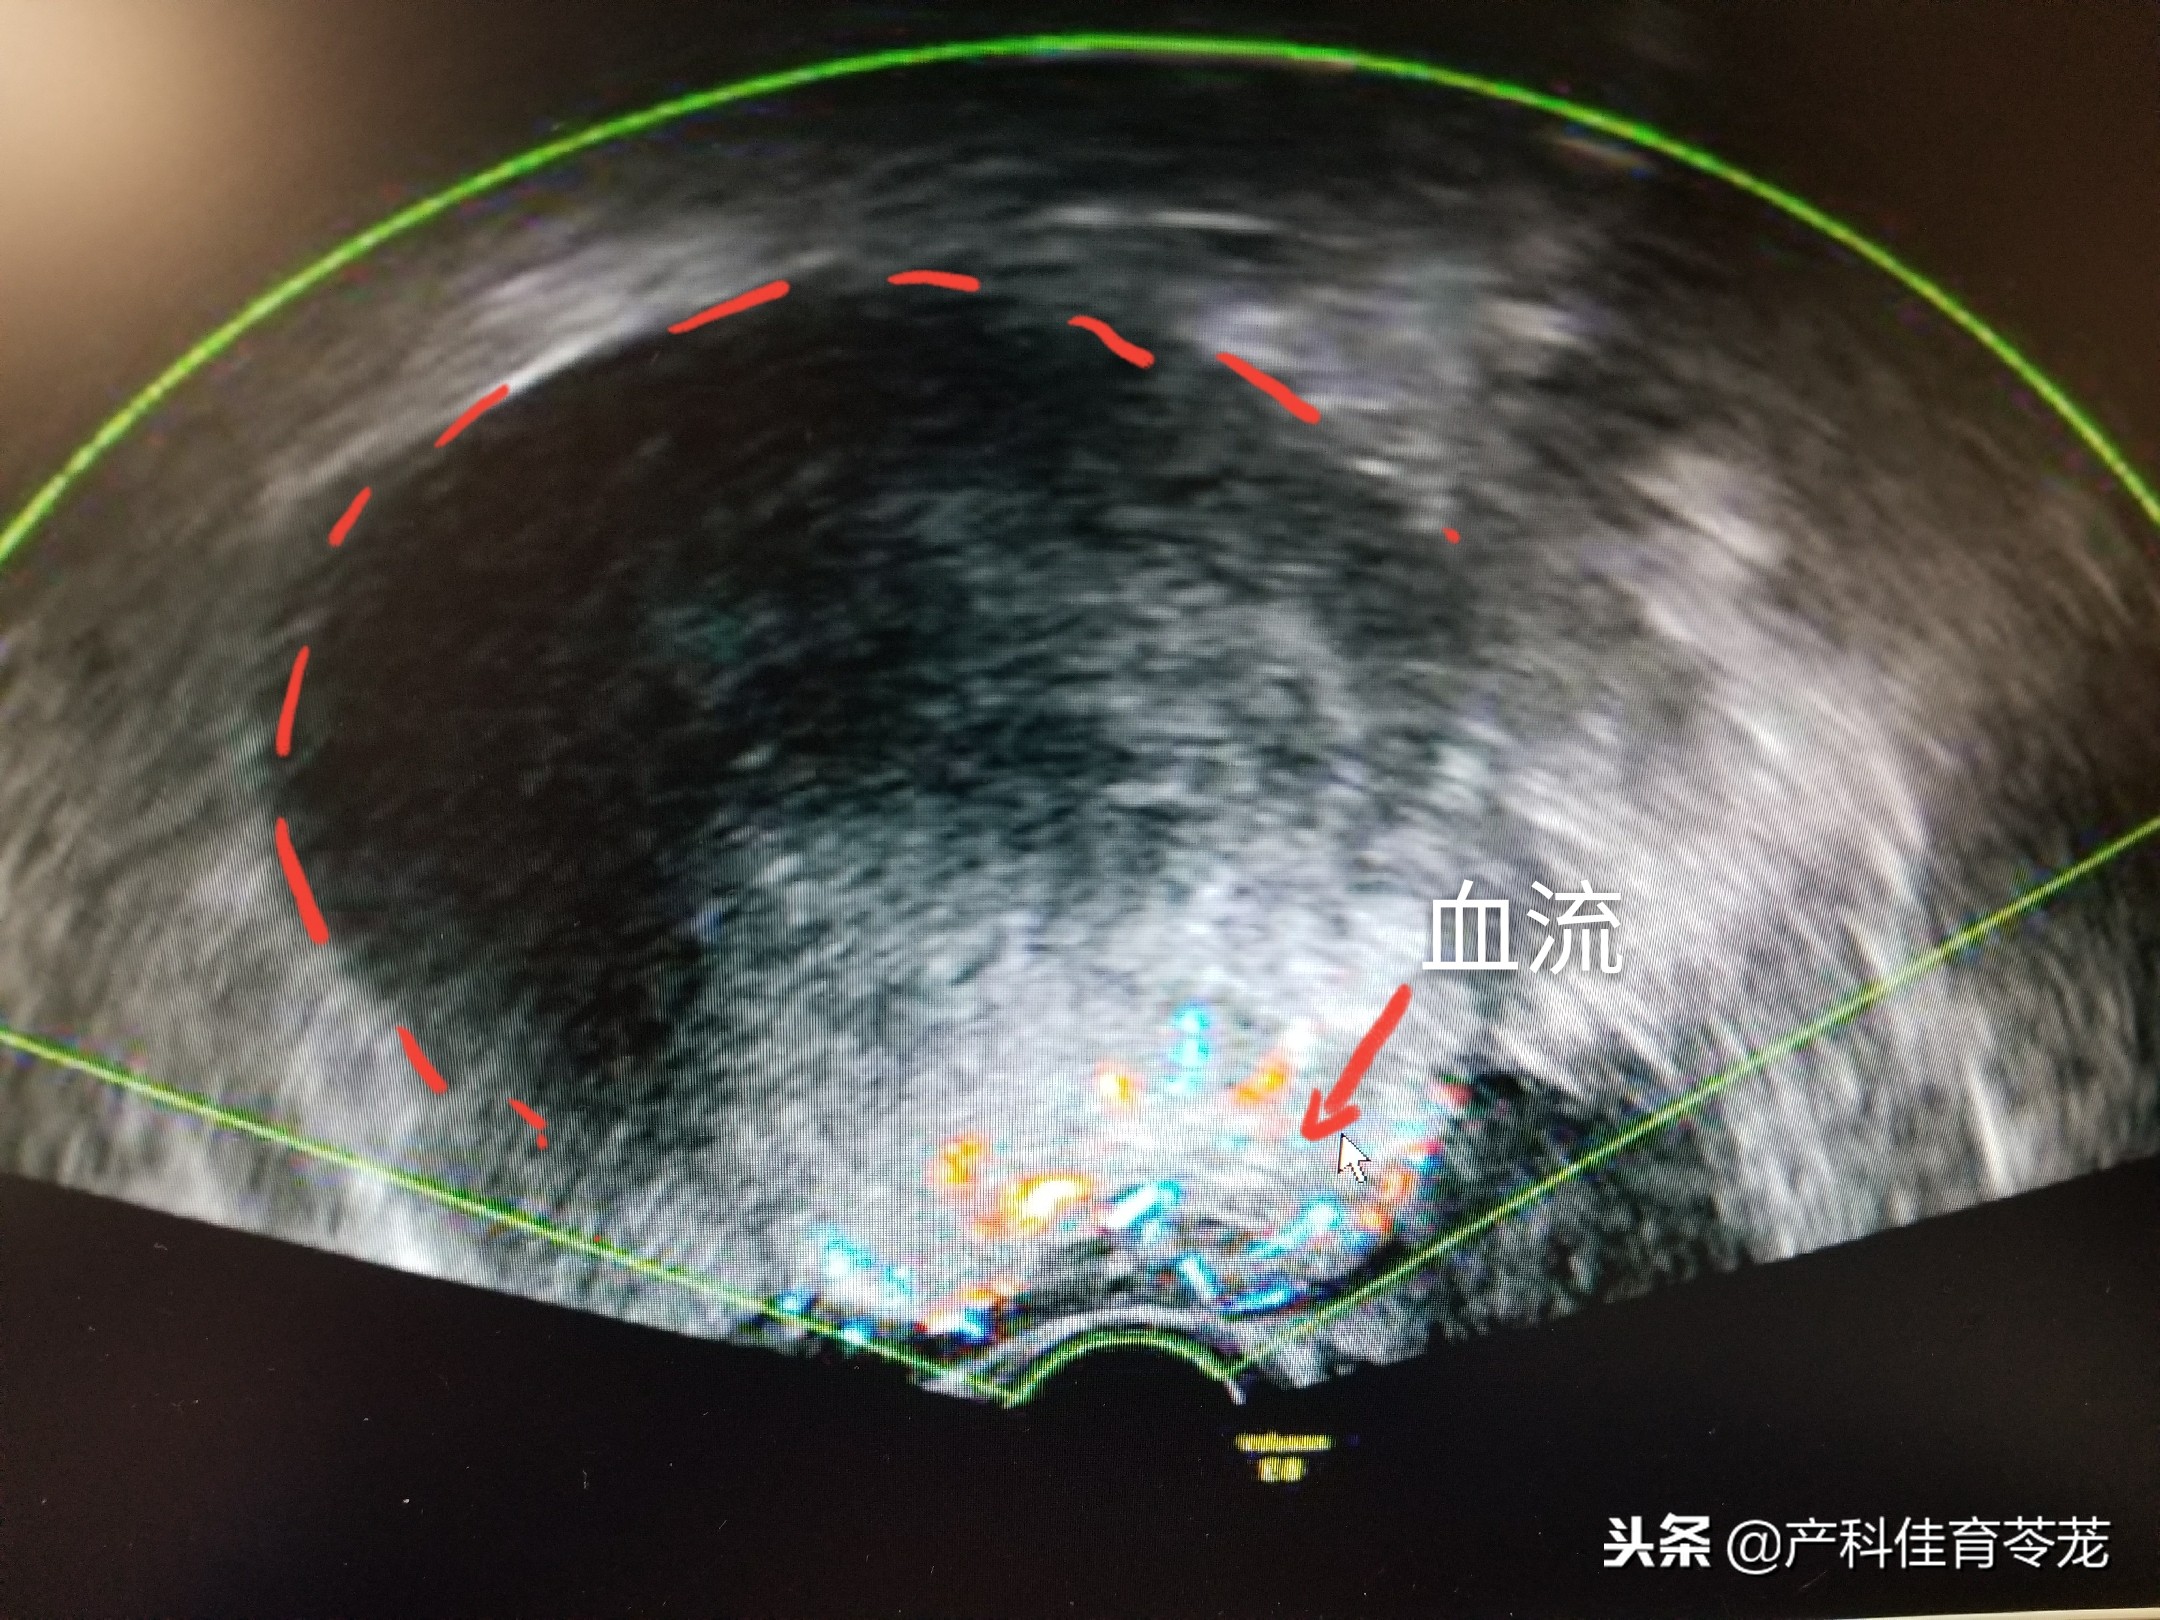

6、卵巢恶性肿瘤:

这种肿瘤里面的成分很复杂,跟周围组织会有粘连,所以B超下的特点是形态多不规则、轮廓模糊、边界不清、壁厚薄不均、内回声强弱不一,呈弥漫性分布的杂乱光点,光团,有出血坏死,囊性变时,可局部形成无回声区,彩色多普勒可见丰富血流信号。常同时合并有腹水。

看到这里,您可能会说,良性肿瘤和恶性肿瘤的B超图像太像了,仔细对比一下,会发现良性的边界更清楚、形态比较规则,里面大部分是液性暗区(黑色区域),而恶性的边界不是很清楚,形态也不是很规则,里面除了液性暗区,还有杂乱的回声(发白的区域),血流相对更丰富。